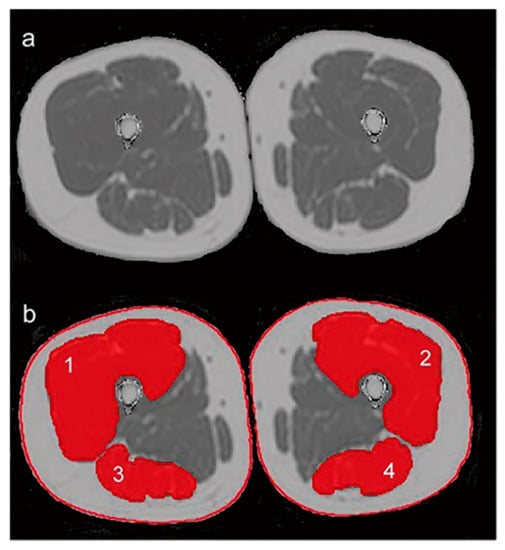

- Edmunds, K.; Gíslason, M.; Sigurðsson, S.; Guðnason, V.; Harris, T.; Carraro, U.; Gargiulo, P. Advanced quantitative methods in correlating sarcopenic muscle degeneration with lower extremity function biometrics and comorbidities. PLoS ONE 2018, 13, e0193241. [Google Scholar] [CrossRef] [PubMed]

- Inhuber, S.; Sollmann, N.; Schlaeger, S.; Dieckmeyer, M.; Burian, E.; Kohlmeyer, C.; Karampinos, D.C.; Kirschke, J.S.; Baum, T.; Kreuzpointner, F.; et al. Associations of thigh muscle fat infiltration with isometric strength measurements based on chemical shift encoding-based water-fat magnetic resonance imaging. Eur. Radiol. Exp. 2019, 3, 45. [Google Scholar] [CrossRef] [Green Version]